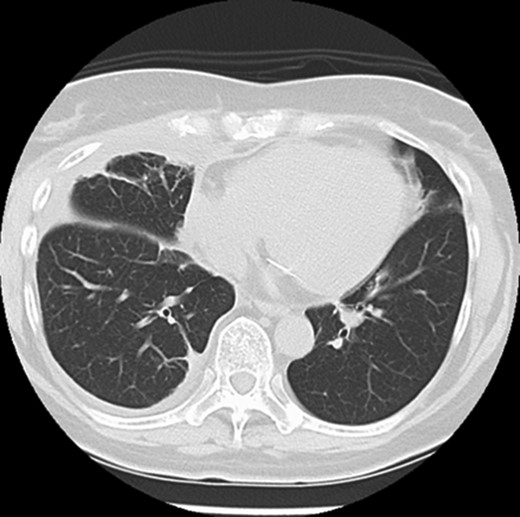

On follow-up CT at 1 month postoperatively, the upper lobe remained in the thoracic cavity and no sign of lung herniation was apparent (Fig. 3).

Follow-up CT shows that the lung hernia has returned to the thoracic cavity.